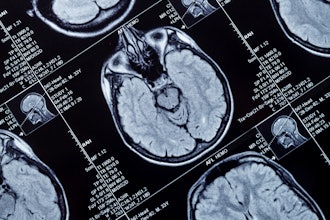

MRI identifies parts of the brain that remember words